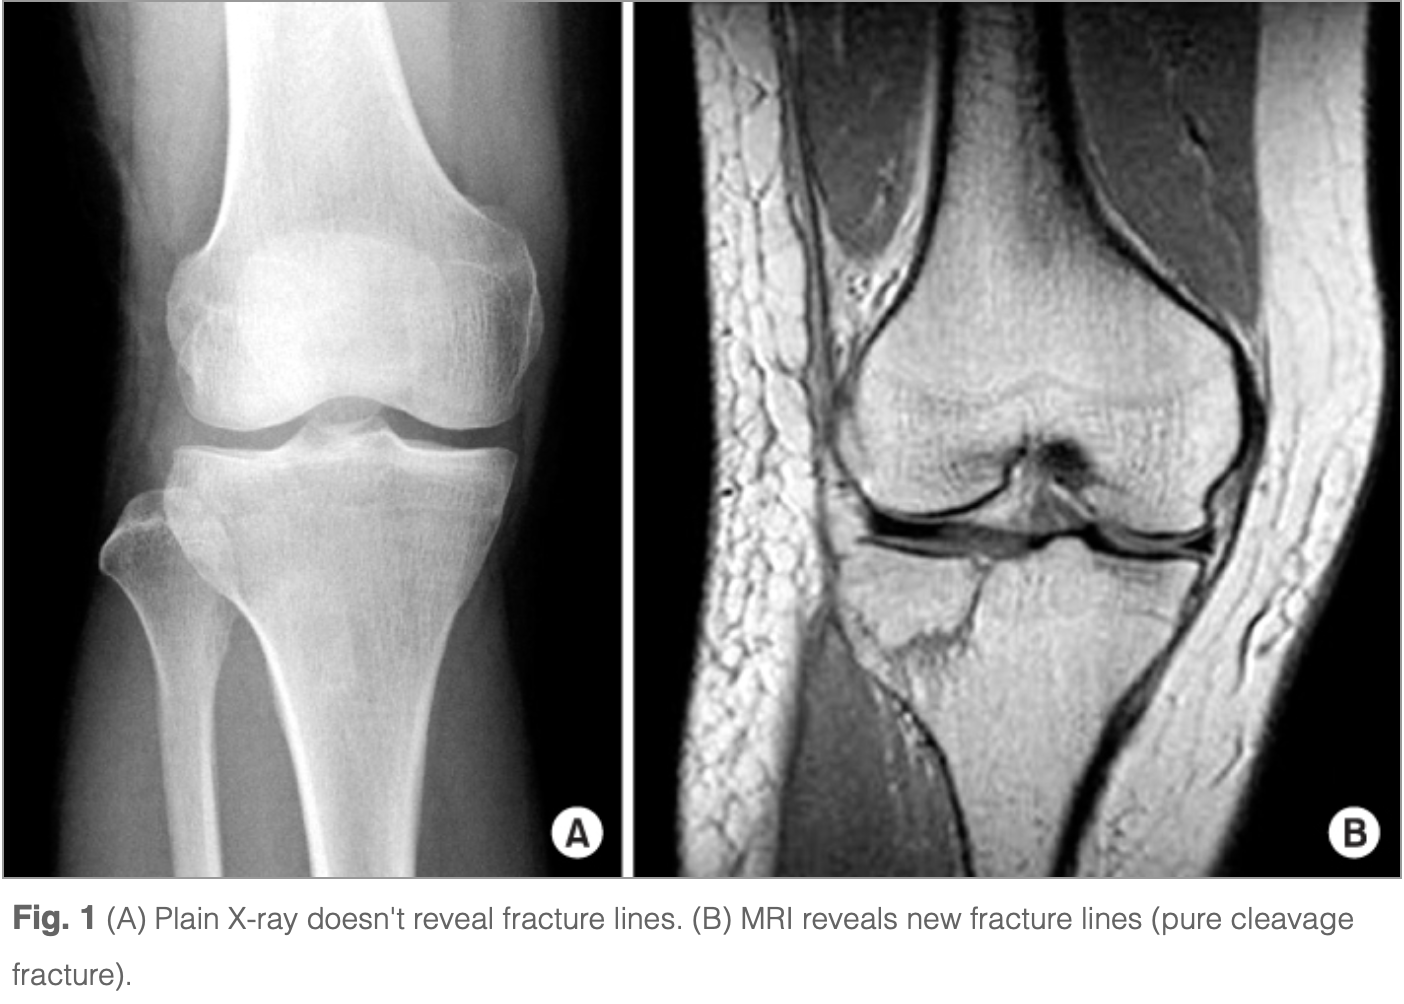

X線写真(左上A)では, 骨折は不明瞭ですが, MRI(右上B)では, 骨の中に黒い線があって, 骨折があることが判ります.

膝関節のX線写真には異常はありませんでしたが, MRIでは脛骨の膝関節部分の外側(外顆)と腓骨の先端部(腓骨頭)の中に骨折があることが判りました. 骨粗鬆症による脆弱性(ぜいじゃくせい)骨折と判断しました.